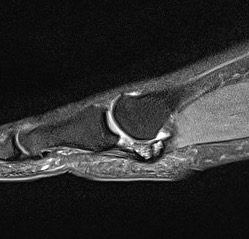

CT demonstrates irregular borders consistent with fracture of tibial sesamoid

Edema on T2 MRI indicates likely acute fracture

Tibial sesamoid stress fracture in a marathon runner